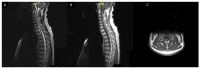

Sarcoidosis is a multi-system disease of unknown etiology characterized by the formation of granulomas in various organs. It affects people of all ethnic backgrounds and occurs at any time of life but is more frequent in African Americans and Scandinavians and in adults between 30 and 50 years of age. Sarcoidosis can affect any organ with a frequency varying according to ethnicity, sex and age. Intrathoracic involvement occurs in 90% of patients with symmetrical bilateral hilar adenopathy and/or diffuse lung micronodules, mainly along the lymphatic structures which are the most affected system. Among extrapulmonary manifestations, skin lesions, uveitis, liver or splenic involvement, peripheral and abdominal lymphadenopathy and peripheral arthritis are the most frequent with a prevalence of 25-50%. Finally, cardiac and neurological manifestations which can be the initial manifestation of sarcoidosis, as can be bilateral parotitis, nasosinusal or laryngeal signs, hypercalcemia and renal dysfunction, affect less than 10% of patients. The diagnosis is not standardized but is based on three major criteria: a compatible clinical and/or radiological presentation, the histological evidence of non-necrotizing granulomatous inflammation in one or more tissues and the exclusion of alternative causes of granulomatous disease. Certain clinical features are considered to be highly specific of the disease (e.g., Löfgren's syndrome, lupus pernio, Heerfordt's syndrome) and do not require histological confirmation. New diagnostic guidelines were recently published. Specific clinical criteria have been developed for the diagnosis of cardiac, neurological and ocular sarcoidosis. This article focuses on the clinical presentation and the common differentials that need to be considered when appropriate.